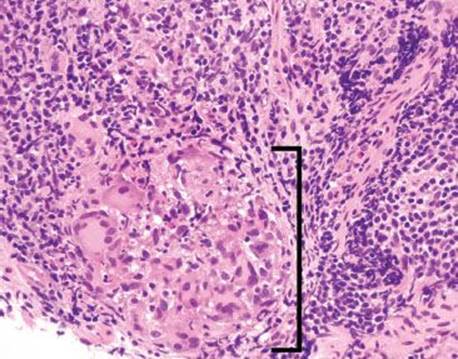

Figure 3.53 Acute ileitis pattern, aphthoid lesion. Higher power of previous case. An aphthoid lesion/ulcer refers to acute inflammation in the epithelium overlying a lymphoid aggregate. In the appropriate clinicopathologic context, an aphthoid lesion can lend support to the diagnosis of Crohn disease.

When assessing the acute ileitis pattern, it is worthwhile to carefully scrutinize the background mucosa for any additional diagnostic clues that might help refine the diagnosis. For example, aphthoid lesions/ulcers consist of acute inflammation in the epithelium overlying lymphoid aggregates and their presence can lend support to a clinicopathologic diagnosis of Crohn disease (Figs. 3.52–3.54). Although granulomata can be difficult to detect in the normally busy-appearing terminal ileum biopsies, their presence can also be helpful when considering the possibility of Crohn disease, infection, sarcoidosis, or medication injury (Figs. 3.58–3.65). Features of chronic mucosal injury are also important to identify, such as pyloric gland metaplasia and architectural distortion, although these features can be seen with chronic injury of any sort, such as chronic NSAID-associated injury or chronic infections (Figs. 3.58–3.73). Histologic features of chronic mucosal injury are extensively discussed in Chronic Colitis, Colon Chapter. Based on the overlapping features between IBD, chronic medication injury, and chronic infection, IBD is remains a clinicopathologic diagnosis that must encompass all available clinicopathologic features (clinical symptomatology, disease course, disease distribution pattern, pertinent microbiologic studies, and family history, etc.).13